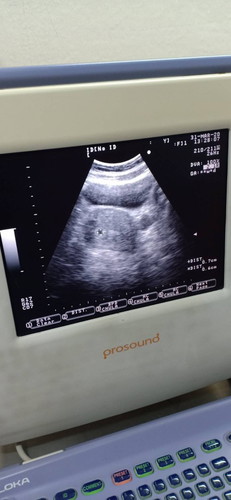

วันนี้ไปฝากครรภ์และอัลตราซาวด์มาค่ะ เจอถุงเล็กๆ หมอนัดอีกที21เมษายน แต่มีอาการปวดท้องเสียดๆช่วงบนแถวลิ้นปี่บ่อยมาก จะเป็นอันตรายมั้ยคะ กังวลมากกลัวเป็นท้องลม